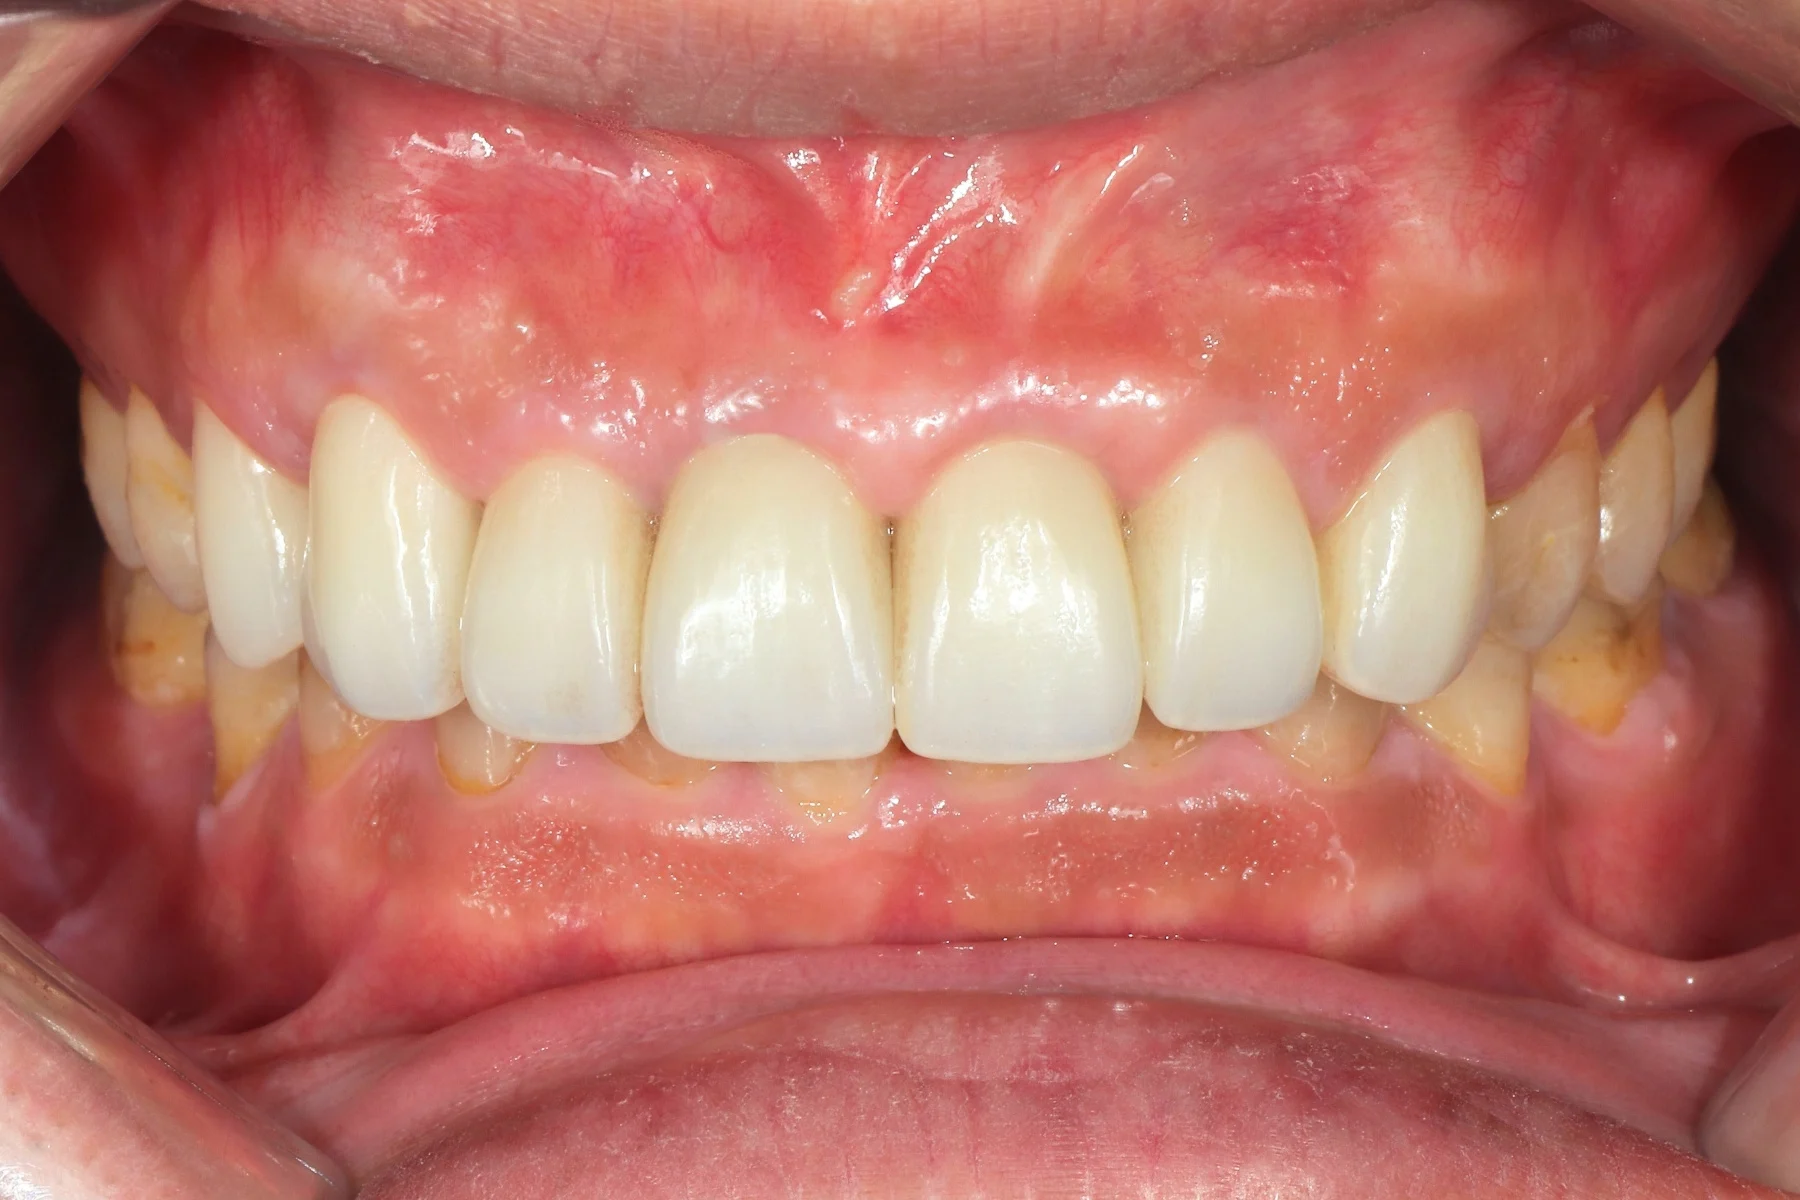

Dentist 陳昕 全口照護醫師 看診項目 前牙美學仿生樹脂補牙/全科牙醫 學經歷 臺北醫學大學牙醫系學士 前天主教新店耕莘醫院醫師 前臺北榮民總醫院醫師 亞洲齒列再生研究學會Advance植牙補綴專科訓練 微光私塾牙周雷射微創治療技術訓練 臺灣牙醫顯微美學治療學會會員醫師 中華審美牙醫學會會員醫師 CASE 案例分享 滲透型樹脂修復 主治醫師 陳昕 治療時間 單次療程 主訴 想處理前牙白白的色斑 前牙美學/仿生美學樹脂 主治醫師 陳昕 治療時間 單次療程 主訴 牙齒整齊,但門牙中間縫隙明顯,影響笑容美觀 前牙美學/陶瓷貼片 主治醫師 陳昕 治療時間 約1個月 主訴 兩顆門牙缺角,想要重建外觀 前牙美學/滲透型樹脂修復 主治醫師 陳昕 治療時間 單次療程 主訴 門牙有長期存在的白斑與表面不平整,影響外觀與自信 前牙美學/仿生美學樹脂 主治醫師 陳昕 治療時間 約兩週 主訴 矯正後的黑三角縫問題 前牙美學/仿生美學樹脂 主治醫師 陳昕 治療時間 約三週 主訴 因牙周病產生的黑三角縫 前牙美學/牙冠增長術、仿生全瓷牙冠 主治醫師 陳昕 治療時間 約6個月 主訴 牙齒排列不整、假牙外觀不自然 前牙美學/仿生美學樹脂 主治醫師 陳昕 治療時間 約兩週 主訴 露齒笑時黑三角縫明顯,覺得不好看 前牙美學/仿生美學樹脂+噴砂美白 主治醫師 陳昕 治療時間 約兩週 主訴 露齒笑時有不好看的黑三角縫,容易有茶垢沉澱,讓縫隙更明顯 牙齒美白/噴砂美白+冷光美白 主治醫師 陳昕 治療時間 單次療程 主訴 前牙泛黃且染色明顯,影響外觀與自信 牙齒美白/噴砂美白 主治醫師 陳昕 治療時間 單次療程 主訴 牙齒表面有喝咖啡、抽菸造成的外部染色,影響外觀與自信 點此載入更多 Column 精選文章 FEATURED 精選案例 【牙科修復案例】陶瓷貼片可以做一顆嗎?單顆門牙缺角修復,陶瓷貼片重建自然笑容 2026-01-16 從「假笑」到「自然笑容」的轉變——認識「牙冠增長術」與「仿生全瓷冠」 2025-10-14 Video 精選影音